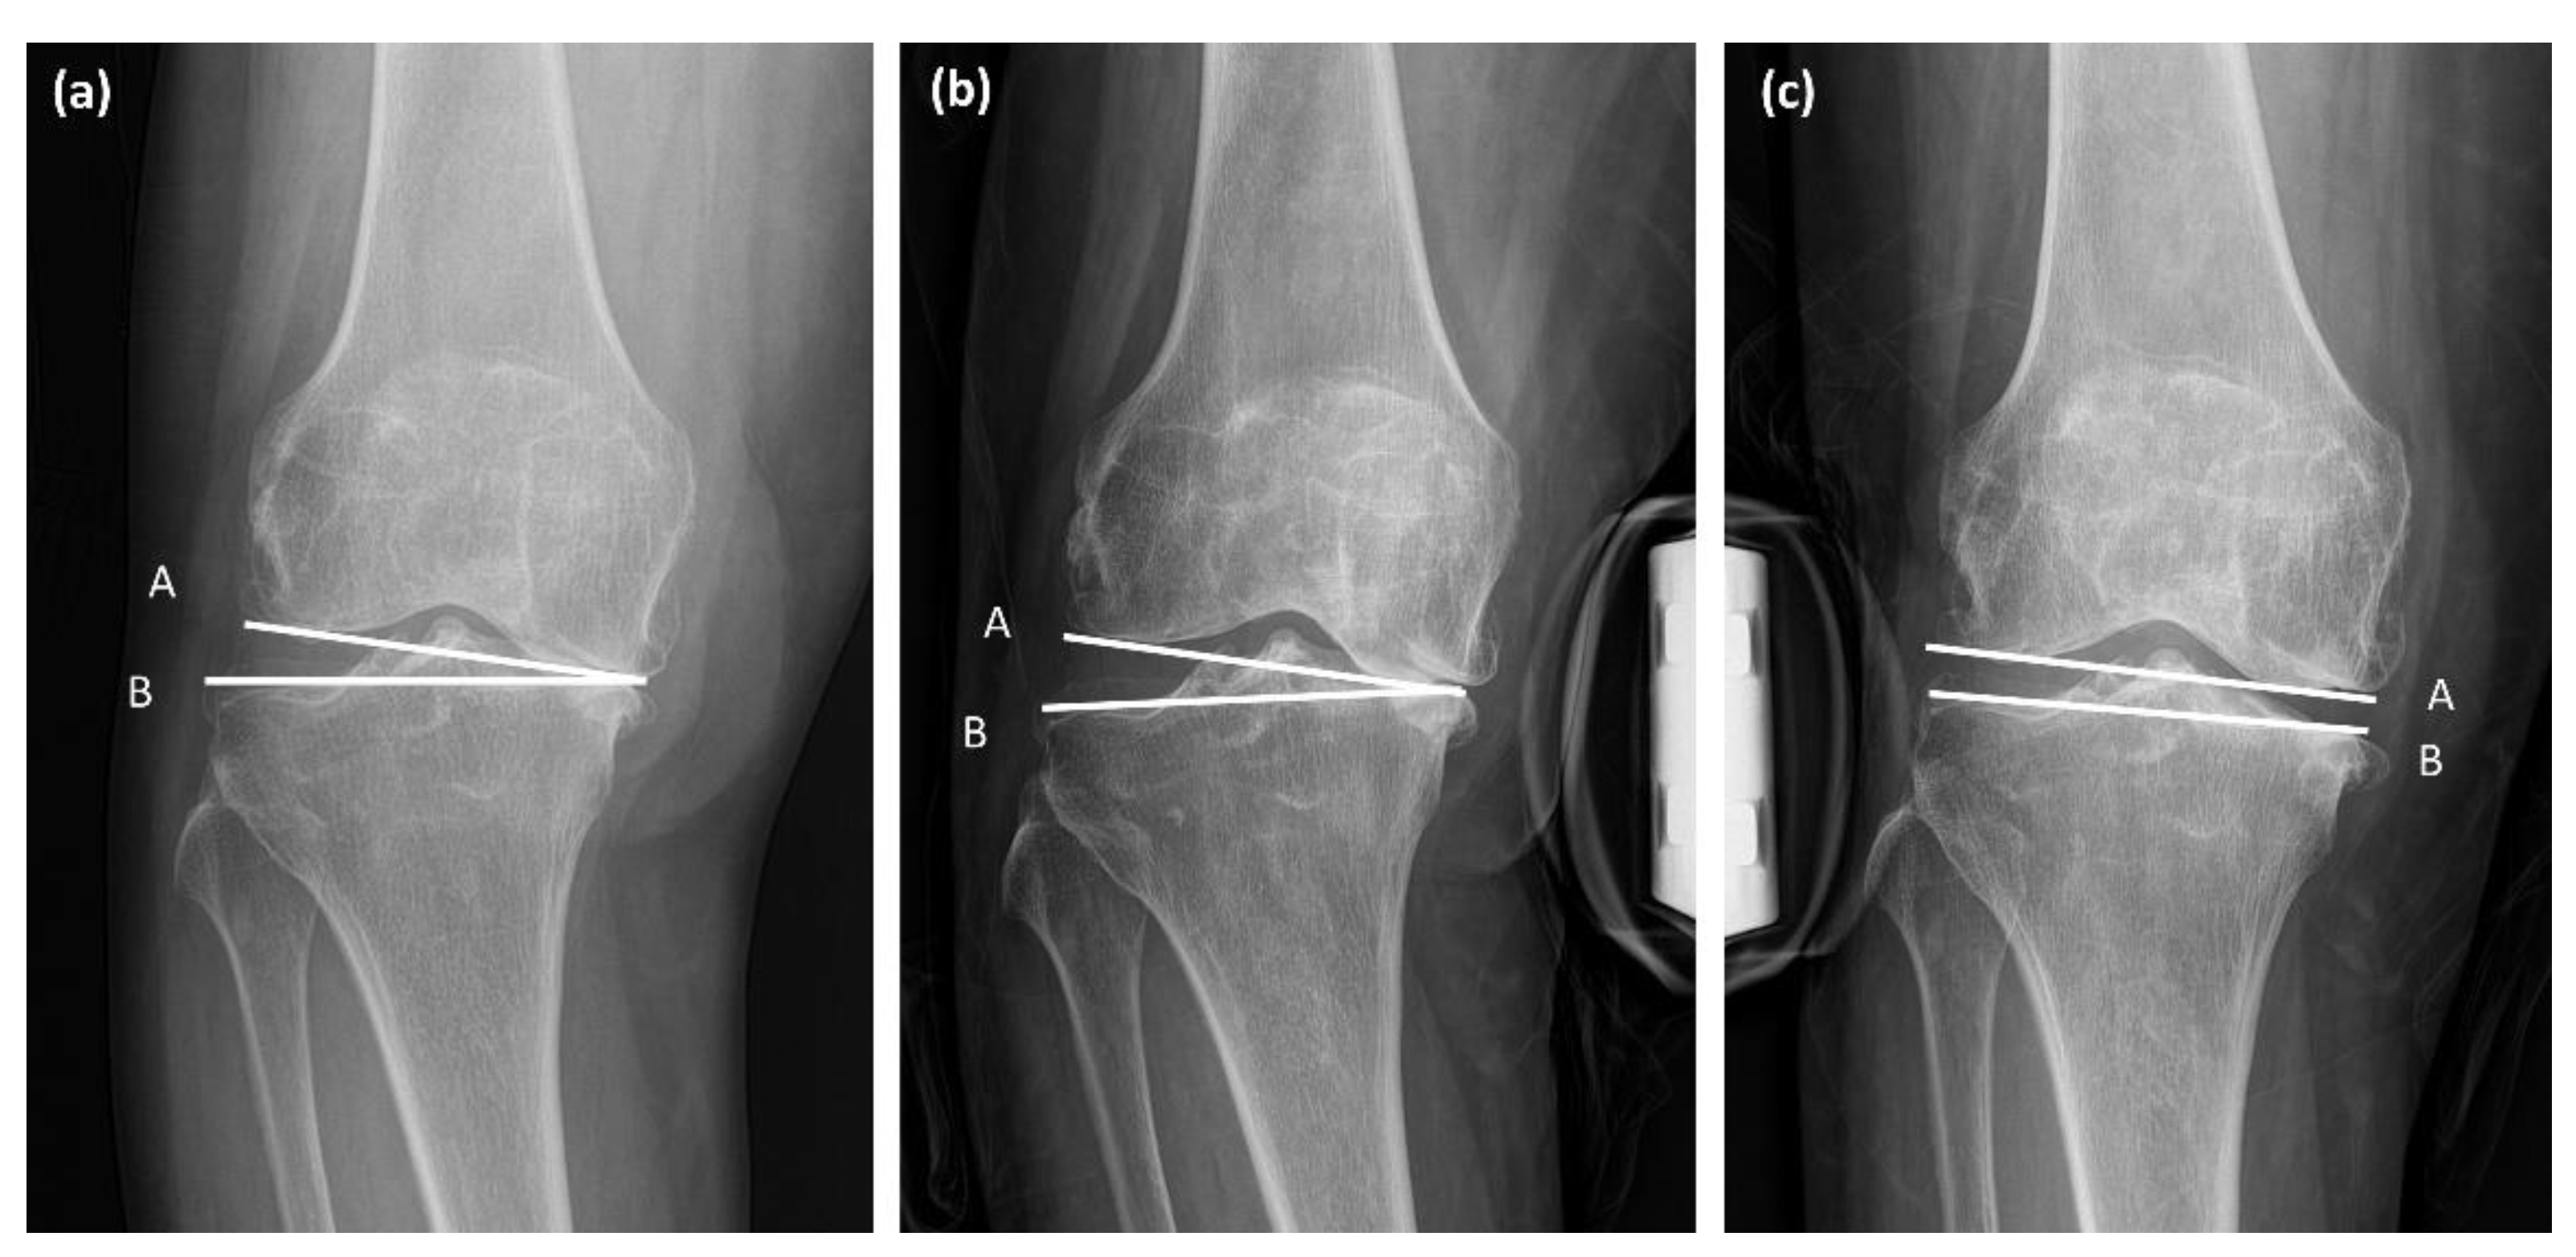

Figure 4.

Measurement of joint line convergence angle (JLCA) and varus/valgus stress JLCA. Line A and B is the line connecting the articular surface of the distal femur and proximal tibia. (a) JLCA standing; (b) JLCA under varus stress; (c) JLCA under valgus stress.

The lateral soft tissue laxity of the knee also contributes to mediolateral gap differences during TKA. Knee osteoarthritis with severe varus deformity is associated with tightened medial soft tissue structures and lax lateral structures [38]. In the present study, we assessed medial and lateral soft tissue tension using the JLCA on standing anteroposterior and varus/valgus stress radiographs (Figure 3). The results demonstrated that lateral ligament laxity (JLCA under varus stress) was significantly larger in the severe varus deformity group than in the mild varus deformity group. This was determined to be an influencing factor for both FGD and EGD. However, the medial ligament laxity (JLCA under valgus stress) showed no statistical difference between the severe and mild varus deformity groups. The pathogenesis of lateral soft tissue laxity in varus osteoarthritic knees is believed to be related to the adduction moment of the knee [37,39]. In osteoarthritic varus knees, the ground reaction force passes far medially to the center of the knee and produces the knee adduction force [19]. Weight-bearing as a part of daily activities increases the adduction moment and aggravates the laxity of the lateral soft tissues [37].